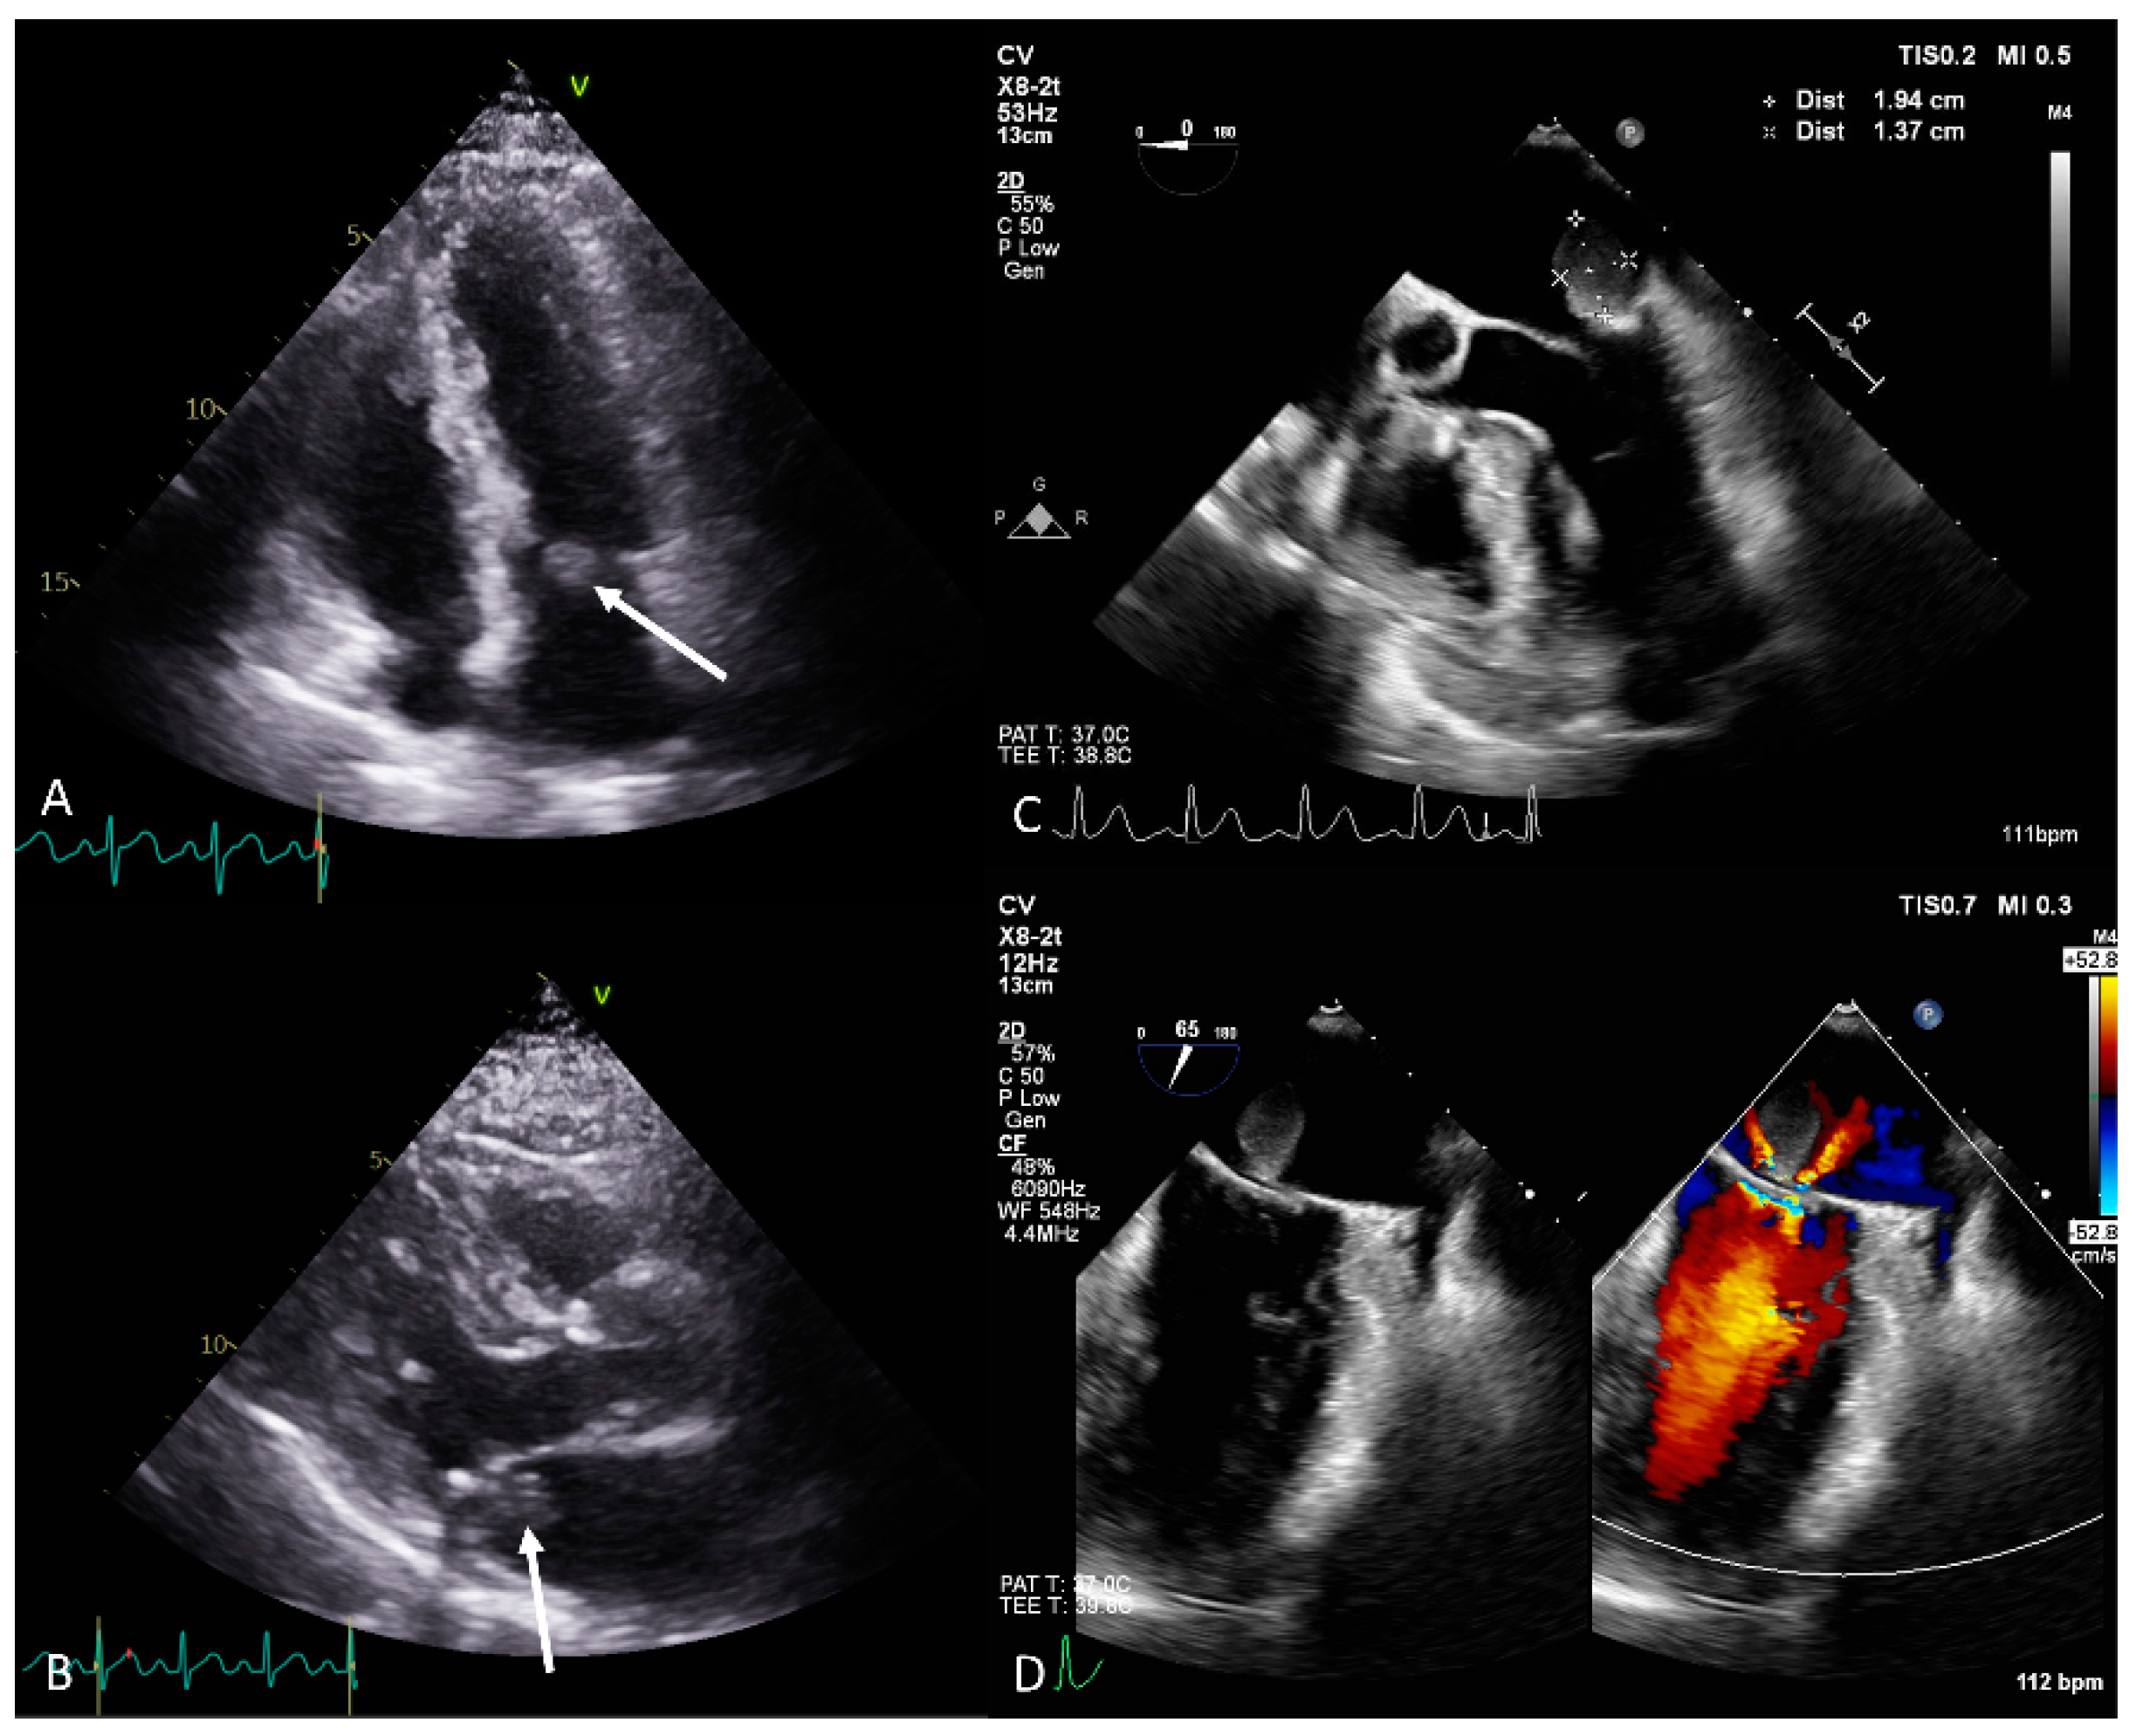

A 70-year-old man presenting with chills and cold sweats was transferred to the emergency room. An echocardiogram revealed a mobile 1.57 × 2.47 cm mass on the mitral valve (Figure 1A,B); consequently, vegetation was suspected (details in Supplementary Table S1). The laboratory tests revealed leukocytosis, elevated C-reactive protein levels, and negative blood culture (details in Supplementary Table S2). However, the echocardiologist questioned the diagnosis because of the mass’s smooth, well-defined shape (differential diagnosis in Supplementary Table S3). Transesophageal echocardiography identified a 1.9 × 1.4 cm polypoid mass with a pedicle attached to the annulus near P2, suggesting a tumor (Figure 1C,D). During surgery, a round 1.5 × 1.5 × 1.5 cm tumor was identified at the mitral annulus between P1 and P2 that was connected to underlying mitral annulus calcification (Figure 2A,B). The tumor and a small part of the annulus endocardium were excised, and a mitral ring annuloplasty was performed. Pathology confirmed the diagnosis of hemangioma with dense lymphocyte infiltrate (Figure 2C,D). Postoperative echocardiography revealed no mitral regurgitation. Previous reports have mentioned that hemangiomas on the mitral valve may cause multiple brain infarcts [3]. Other types of intracardiac tumors, such as cardiac papillary fibroelastoma, have also been misdiagnosed as infective endocarditis [4]. Through this case, we hope to offer clinicians with additional perspectives for the diagnosis and management of intracardiac mass lesions.

Figure 2. (A) A round 1.5 × 1.5 × 1.5 cm tumor at the mitral annulus between P1 and P2. (B) A tumor on the posterior mitral annulus connected to underlying mitral annulus calcification. (C) Pathology showed hemangioma with dense lymphocyte infiltration (5× magnification). (D) CD34 stain revealed a capillary–cavernous hemangioma with dense lymphocyte infiltration (10× magnification).